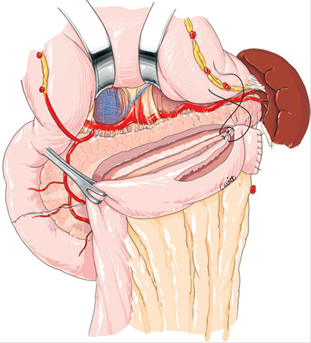

Sección del intestino delgado a nivel de la segunda asa yeyunal, con cierre del extremo distal de la misma y ascenso del asa por vía transmesocólica. Apertura del asa por su borde antimesentérico y confección de la anastomosis yeyuno-pancreática (Wirsung) latero-lateral con puntos separados con poliglactina en 2 planos (Figura 3).

Fig. 3: Derivación Wirsung-yeyunal. Apertura del conducto de Wirsung por su cara anterior y apertura del asa yeyunal por su borde antimesentérico. Anastomosis Wirsung-yeyunal. Tomado de (6).

En 1958, Puestow y Gillesby (3) describe la técnica que lleva su nombre que consiste en una pancreatectomía distal, esplenectomía y derivación del conducto pancreático mediante inserción del páncreas en una yeyunostomía en Y de Roux. Posteriormente, en 1960, Partington y Rochelle (4) describen la sutura del conducto pancreático a un asa yeyunal, logrando de esa manera la derivación del conducto pancreático y evitando la resección pancreática y esplénica. Dicho procedimiento se conoce actualmente como derivación Wirsung-yeyunal, pancreático-yeyunostomía latero-lateral, procedimiento de Puestow modificado o de Partington – Rochelle (Figura 3).